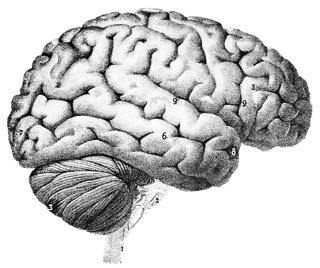

Parkinson’s and parkinsonism — symptoms that mimic Parkinson’s — stem from the same areas of the brain. These disorders both cause tremors, stiffness, slowness of movement, however they have different causes and may be helped with different nutritional therapies. Parkinson’s versus parkinsonism It’s helpful to know the difference between the two. Parkinson’s is a disease that slowly destroys brain cells (for some people it happens quickly) in an area of the brain that produces the brain chemical dopamine. Symptoms worsen over the years and include resting tremors, stiffness, slowness, not blinking enough, loss of smell, digestive problems, depression, and dementia....